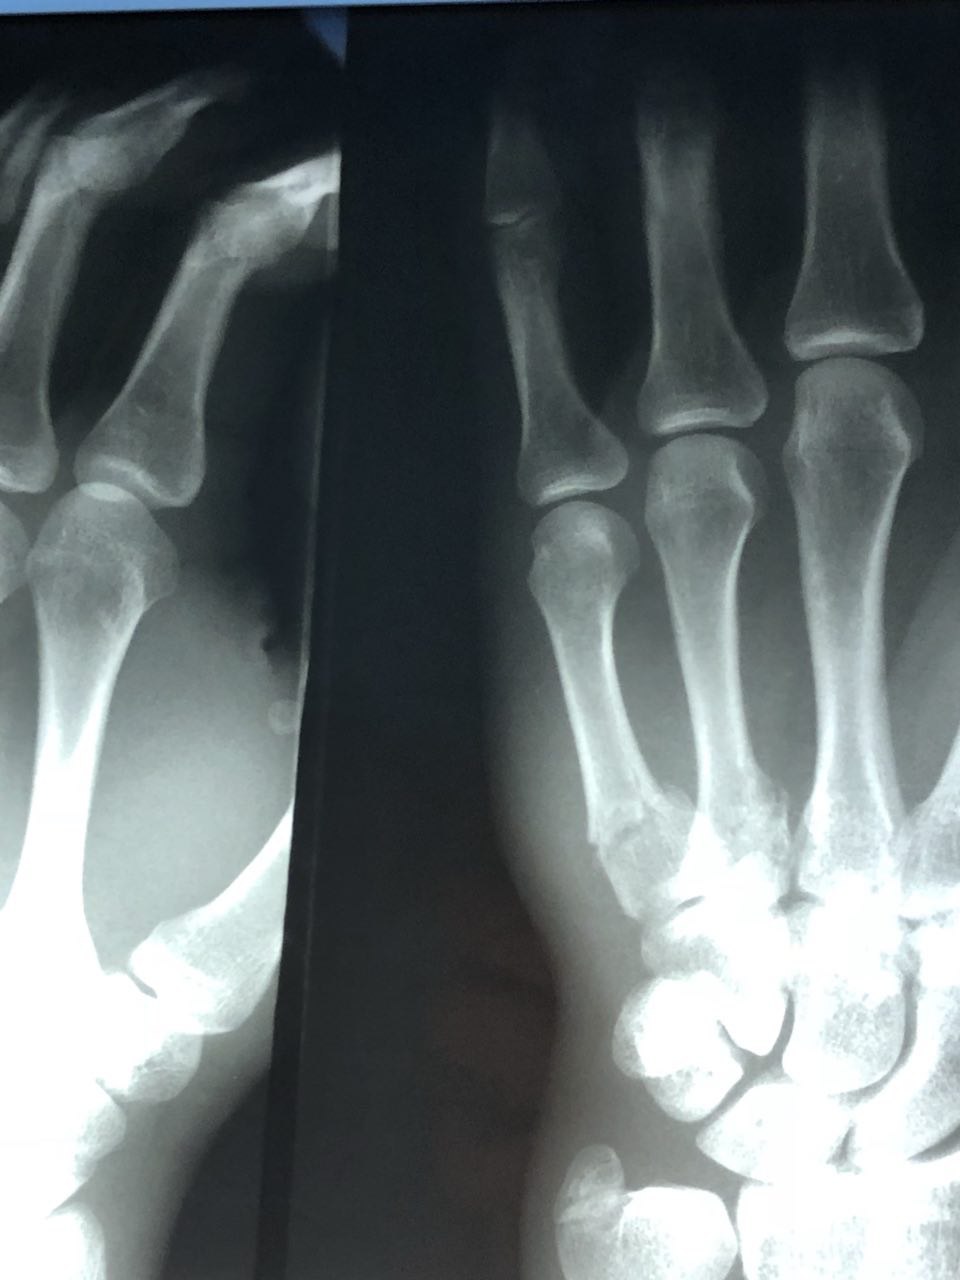

Монтаж клипа затянется ещё на сутки-двое, походу. Сколько переломов насчитаешь? Ответы в чат.

Клип уже вот-вот. С ломаной рукой монтировать жестко. Ориентир: сегодня-завтра.  Никому.